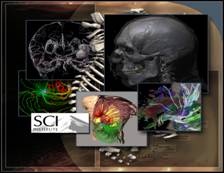

Course Overview. This course provides an introduction to Scientific Visualization techniques used for the effective presentation of data from a variety of disciplines including medicine, engineering, physics and biology. Students will learn about the use of fundamental approaches (color map selection, isocontouring, volume rendering, streamlines, etc…), as well as efficient algorithms for their computation. Special emphasis will be given to the correctness of the results provided, and the reliability of the insight provided to the users/scientists. In the study of visualization algorithms we will emphasize the selection of efficient data structures, complexity analysis, practical efficiency, and verification of the quality of the output generated. Successful completion of the course will enable the students pursuing new research directions in this field as well as applying the most recent visualization techniques for the presentation of data from simulations and experiments and aid the users in the science discovery process.